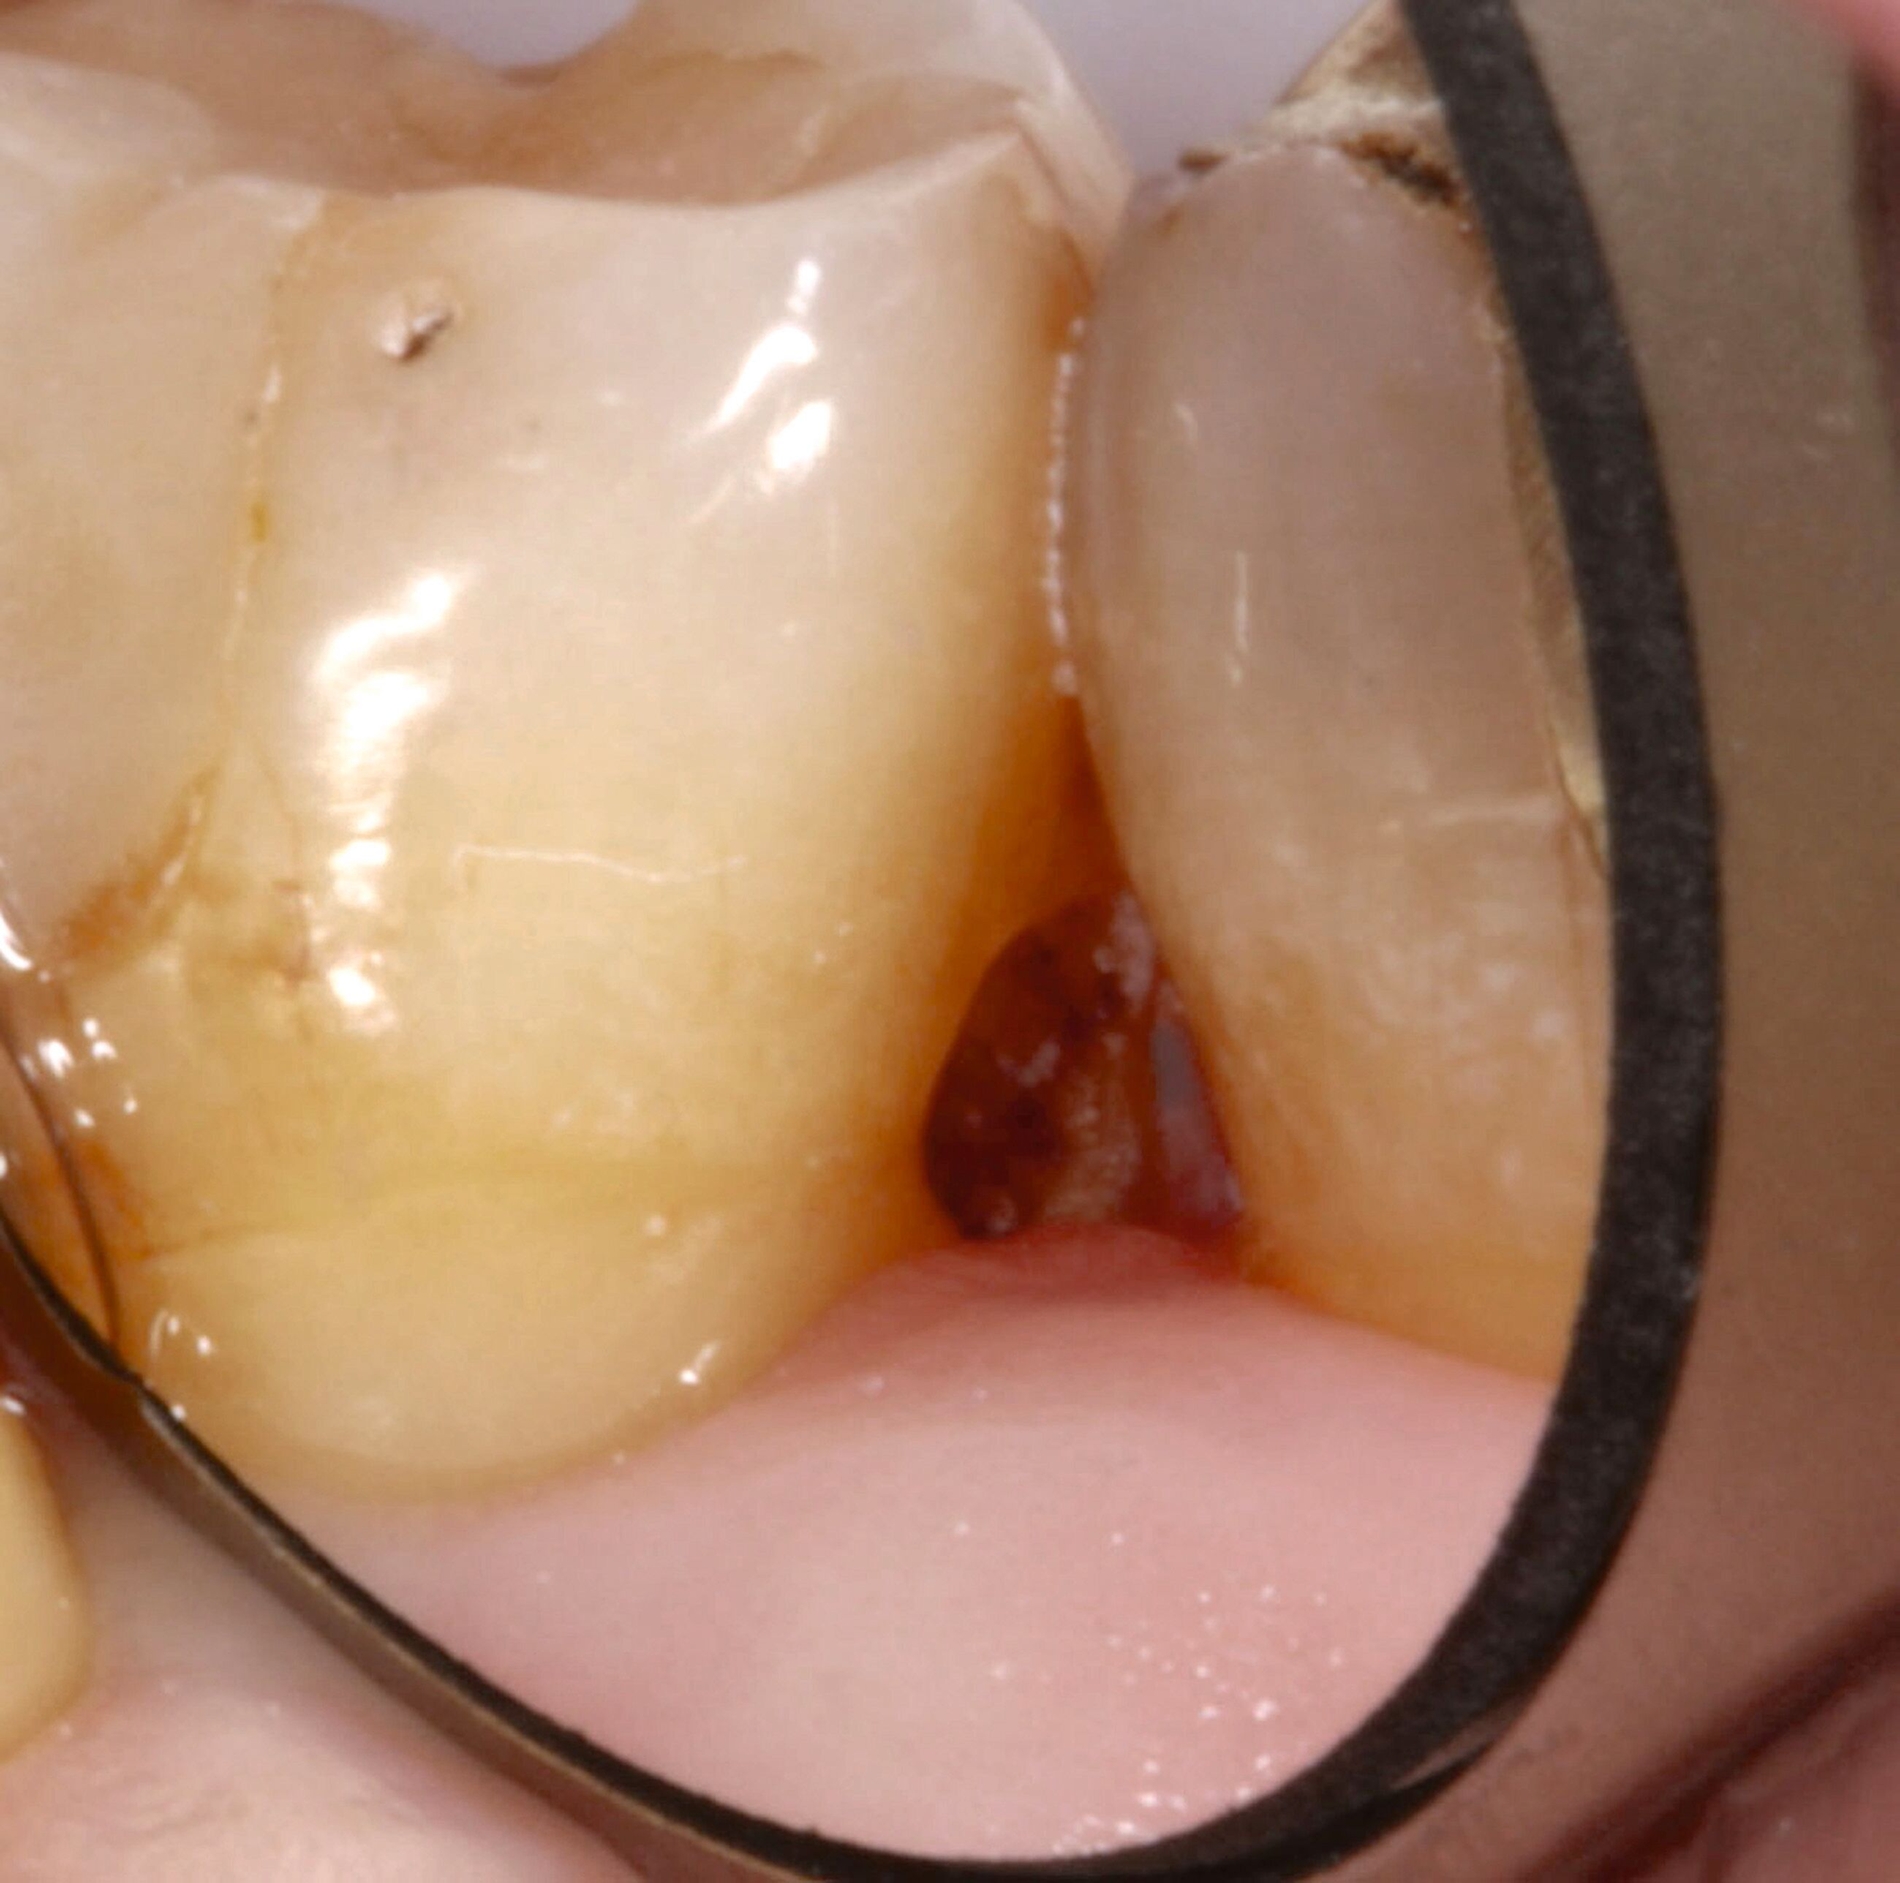

Wurzelkaries kann alle Bereiche der Wurzeloberfläche betreffen und ist in der Regel an Plaqueretentionstellen etwa im Bereich des Gingivarandes, der Kronenränder, der Einziehungen der Wurzeloberfläche oder des Interdentalraums lokalisiert. Zur klinischen Diagnostik sollte zunächst Plaque möglichst vollständig entfernt werden, um interdentale Bereiche einsehen und aussagefähig sondieren zu können. Während die Oral- und die Vestibulärflächen relativ einfach zu befunden sind, sollten die Interdentalräume unter guter Trockenlegung und Ausleuchtung beurteilt werden. Bei ausgedehnten Rezessionen ist die Diagnostik auch interdental gut möglich (Abbildung 4).

Für die Therapieentscheidung ist es essenziell, zwischen aktiven und inaktiven Läsionen zu unterscheiden (Abbildung 6). Die Farbe der Läsion ist zwar kein verlässliches Diagnosekriterium, aktive Wurzelkaries hat aber eher eine gelbliche oder hellbraune Farbe, ist in der Regel von Plaque bedeckt und fühlt sich bei mäßigem Sondieren weich oder ledrig an. Solche Läsionen bedürfen einer Intervention. Inaktive oder arretierte Läsionen haben in der Regel eine dunklere Farbe, sind meist plaquefrei und fühlen sich bei Sondieren hart an. Inaktive Wurzelkaries braucht keine weitere Intervention, auch wenn sie kavitiert, aber reinigungsfähig ist. Die Patientinnen und Patienten sollten jedoch über solche Befunde aufgeklärt werden.